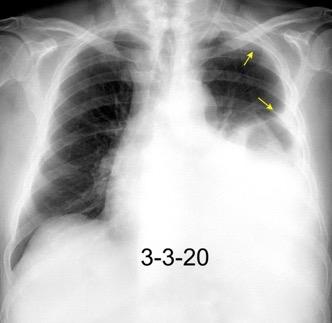

Marzo 2014: Perforación longitudinal distal secundaria a episodio de vómito (síndrome de Boerhaave). Derrame pleural izdo. que evoluciona a empiema.

Wang C-T et al. Tension hydropneumothorax in a Boerhaave syndrome patient: A case report . World J Emerg Med, 2021. Katabathina V et al. Nonvascular, nontraumatic mediastinal emergencies in adults:a comprehensive review of imaging findings. Radiographics. 2011.